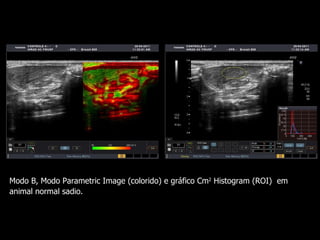

Modo B,  Modo Parametric Image (colorido) e gráfico Cm 2  Histogram (ROI)  em animal normal sadio.